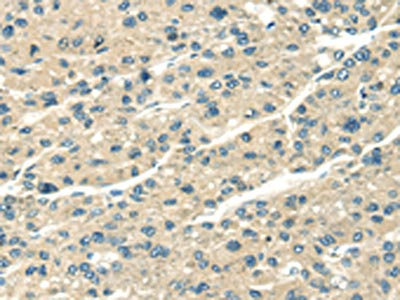

The image on the left is immunohistochemistry of paraffin-embedded Human lung cancer tissue using CSB-PA789238(SERPINA12 Antibody) at dilution 1/40, on the right is treated with fusion protein. (Original magnification: ×200)

The image on the left is immunohistochemistry of paraffin-embedded Human liver cancer tissue using CSB-PA789238(SERPINA12 Antibody) at dilution 1/40, on the right is treated with fusion protein. (Original magnification: ×200)